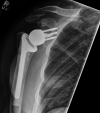

Figures